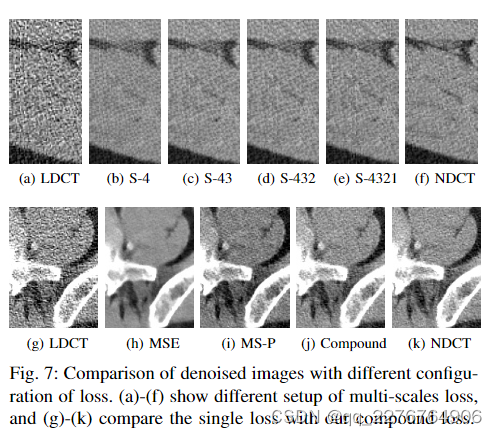

3)多尺度感知损失:当使用感知损失时,我们需要决定使用哪一层特征图。 在这里,我们探讨多尺度感知损失的不同组合。 具体来说,我们利用 ResNet-50 中四个阶段的输出特征(图 3)。 设计了四种类型的损失函数,包括 S-4、S-43、S432 和 S-4321 的感知损失。“S”代表阶段,数字表示用于获取特征图的阶段数。 损失函数将计算这些阶段提取的特征的MSE(方程3),并计算它们的平均值以获得最终的损失值。 图7(a-f)显示了输出图像,我们可以发现,随着使用的级数增加,去噪结果的“纹理”更接近NDCT图像。 因此,我们决定使用ResNet50模型中四个阶段的输出特征来计算我们方法的感知损失。

4)单一或复合损失:在这个实验中,我们获得了三个分别在单一 MSE 损失、单一多尺度感知损失和复合损失上训练的 EDCNN 模型。 他们以同样的方式接受训练,除了损失之外。 如图7(g-k)所示,我们可以比较这些去噪CT图像的视觉质量。 显然,基于MSE的EDCNN模型的结果(图7h)已经过于平滑,为后期诊断遗漏了太多细节,给医生做出判断带来了困难。 至于图7i和图7j,它们在细节保留方面表现出相似的质量,这进一步验证了多尺度感知损失的有效性。 同时,我们可以注意到图7j比图7i稍微清晰一些。 后者引入了一些可见的伪影。 基于复合损失的EDCNN具有更好的性能。